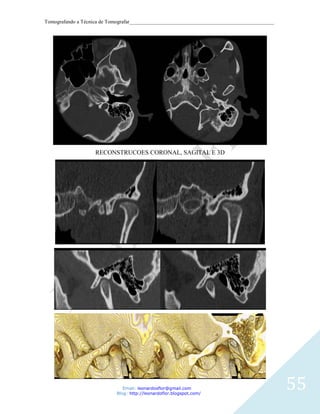

RECONSTRUCOES CORONAL, SAGITAL E 3D

Protocolo

Helical

Thickness (slice): 0.9mm

Increment: 0.45mm

KV: 120

mAs: 150

Resolução: Standard

Colimação: 64x0.625

Pitch: 0.64

Rotação: 0.5 sec

Filtro: Bone (D)

Window: C: 300 / W: 3000

Matrix: 512